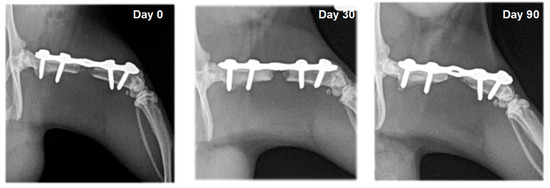

3.2. Radiography